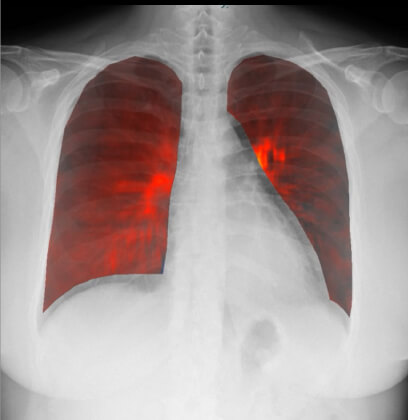

妊娠中に急性肺血栓塞栓症を発症した症例

治療前